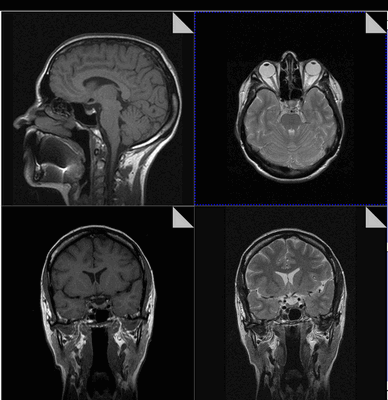

Снимок МРТ головного мозга в двух проекциях

Опухоль гипофиза на снимке МРТ

Фото томографии аденомы гипофиза

Опухоль гипофиза на МРТ выглядит как участок округлой формы с четкими границами

Макроаденома гипофиза на снимке МРТ

Выявление микроаденомы гипофиза с помощью МРТ: изображения в разных проекциях

Гигантская аденома гипофиза на МРТ